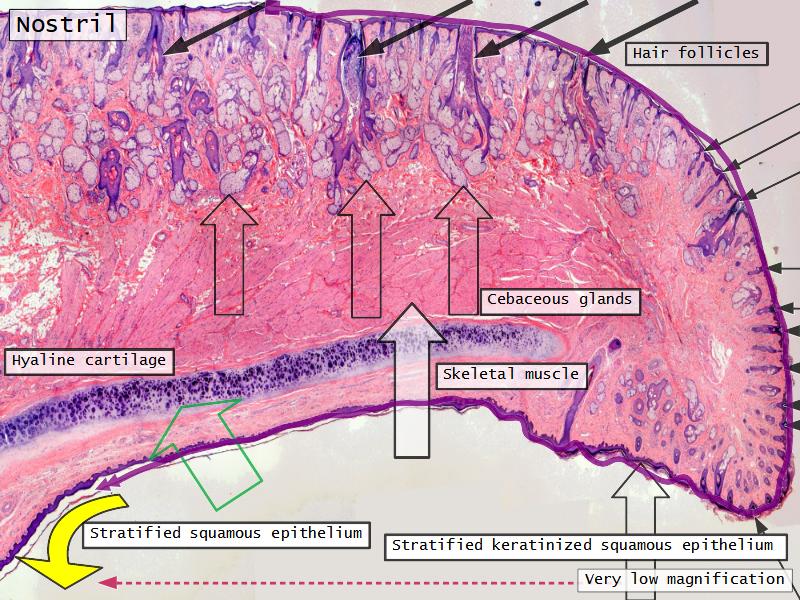

Slides: Respiratory System

- Slide 71: Nostril

Nostril

Name three types of contractile cells.